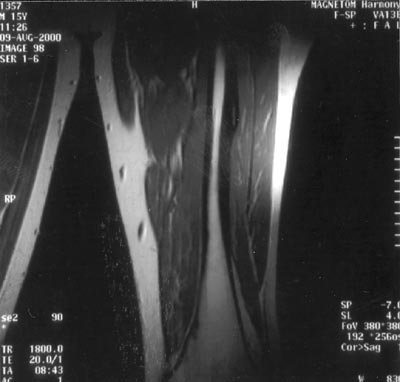

Δύο χρόνια μετά, ο ασθενής δεν έχει παρουσιάσει νέα υποτροπή, ενώ η τελευταία

μαγνητική τομογραφία κατέδειξε πλήρη εξάλειψη του ψευδοόγκου και της οστεοποιού

μυοσίτιδας (εικόνα 3).

Εικόνα 2.

Εικόνα 3.